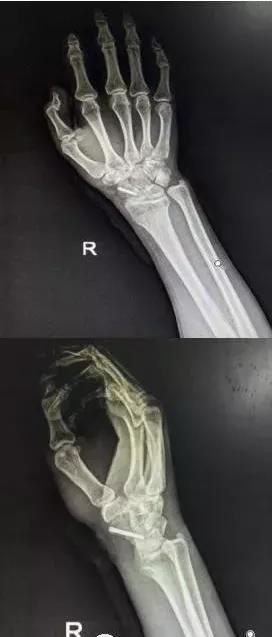

7)手部骨折

- 无论闭合或开放性骨折,均应早期复位内固定。

- 合并神经,血管,肌腱损伤,紧急手术。